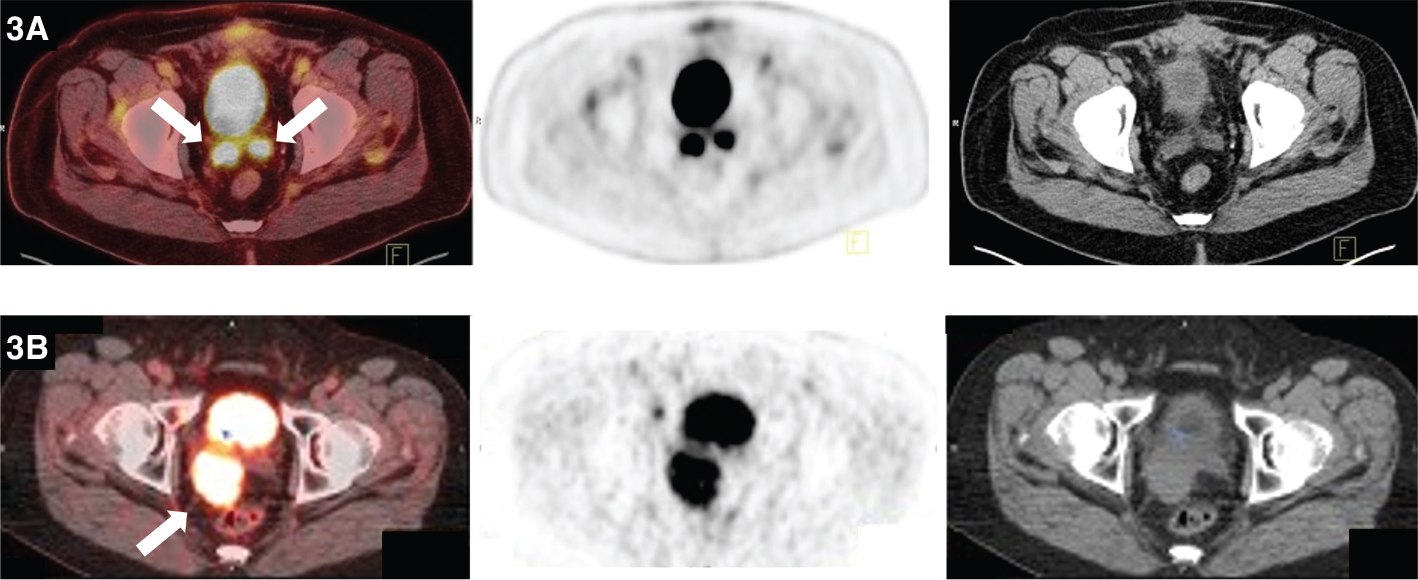

Fig 3

Figure 3. Seminal vesicles. FDG PET/CT demonstrates uptake within the bilateral seminal vesicles (thick solid arrows) in one patient (row 3A) and within an enlarged right seminal vesicle (thick solid arrow) in another patient (row 3B). Biopsy was negative in the first patient suggesting that activity likely represented urinary reflux of radiotracer (3A). Biopsy was positive for a plasmacytoma in the second patient (3B).

Involvement of the seminal vesicles is generally secondary. The most common neoplastic involvement of the seminal vesicles is direct extension of metastasis from prostate, bladder, or rectal cancer, often present upon the initial examination. Metastases from malignancies such as Merkel cell, lymphoma, and hepatocellular cancer have been seen. We present a documented case of plasmacytoma in a seminal vesicle (Figure 3B). Primary malignant neoplasms of the seminal vesicles are relatively rare: adenocarcinoma, sarcoma, leiomyosarcoma, and angiosarcoma are among those noted. A review of the literature showed only approximately 60 reported cases of adenocarcinoma of the seminal vesicles (1619). In the presence of an adjacent malignancy such as prostate cancer, direct extension should be considered. In other settings, metastatic disease or primary seminal vesicle cancer should be considered. As PET/CT findings are usually incidental, there are no established protocols/guidelines for PET/CT imaging of seminal vesicles.